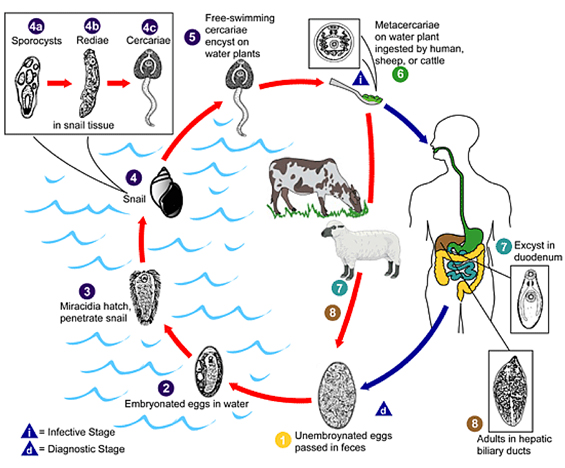

Fascioliasis is a foodborne infection caused by liver flukes Fasciola hepatica and F. gigantica. Transmission occurs from herbivores to humans via ingestion of cysts (metacercariae) present on water plants (classically watercress; see Box) or in contaminated water.1 Fascioliasis affects some of the world’s poorest communities. In the developed world, cases are mainly described in returned travellers, but infection may occur locally through ingestion of imported or locally grown vegetables.2

There are two distinct clinical phases of infection. The parenchymal liver phase is caused by larval migration through the liver, typically 6–9 weeks after infection. Clinically, this manifests as fever, RUQ pain, and eosinophilia. The ductal phase occurs as flukes enter the bile ducts and may cause obstructive jaundice or cholangitis.

Normal eosinophil count cannot be used to exclude parasitic aetiology. Eosinophilia is more likely to be present during the parenchymal phase, however the eosinophil count may be normal in up to 50% of chronic cases.2 Stool microscopy did not yield positive results before treatment in these patients. It is not useful in the acute phase of illness, as the pre-patent period (time from infection to shedding of ova in the faeces by mature adult worms) is 4 months (Box).

Life cycle of Fasciola species*

Fasciola eggs are released in the biliary ducts and faeces (1). Eggs embryonate in water (2), releasing miracidia (3), which invades the intermediate host, the snail (4). Parasites undergo development in the snail (sporocysts 4a, rediae 4b) maturing into cercariae (4c) which are released from the snail (5) and encyst as metacercariae on aquatic vegetation or other surfaces. Domestic or wild ruminants and humans can become infected by ingesting vegetation containing metacercariae (6). Metacercariae excyst in the duodenum (7), migrate through the intestinal wall, the peritoneal cavity, and the liver parenchyma into the biliary ducts, where they develop into adult flukes during a 3–4 month maturation period (8).

*Reproduced (diagram) and adapted (text) with permission from the Centers for Disease Control and Prevention.1